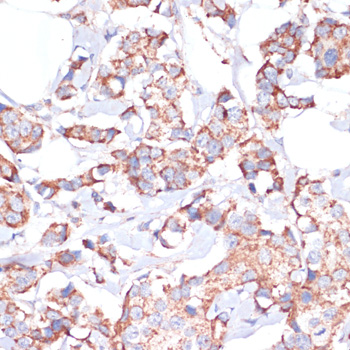

Immunohistochemistry of paraffin-embedded human colon carcinoma using UBE2O antibody.

Immunohistochemistry of paraffin-embedded human breast cancer using UBE2O antibody.

应用详情:IHC 1:50 - 1:200